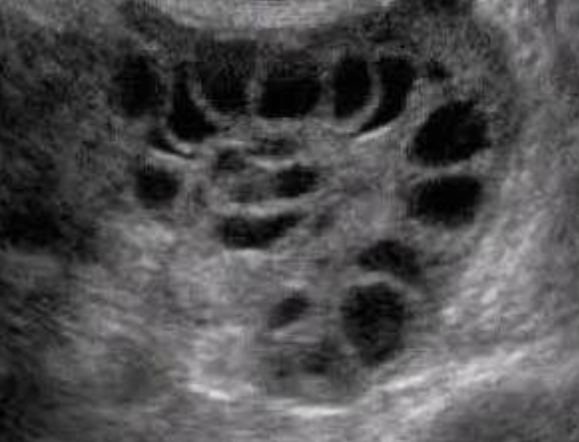

Пациентка пришла с положительным тестом на беременность, по УЗИ - беременность малого срока.